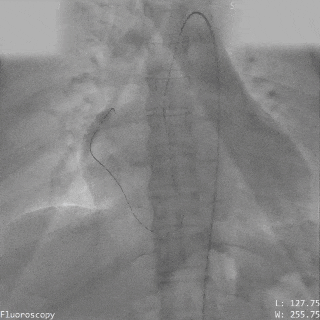

导丝通过主动脉窦瘤破口(左);导丝置于下腔静脉(右)

圈套器抓取导丝建立完整轨道